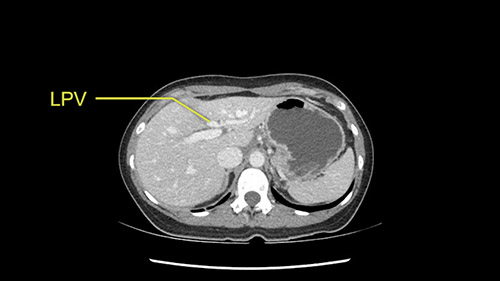

So the issue with regards to resection. A left sided tumor. I believe I can see the falciform ligament right here so we’re looking at a resection of Segments 2, 3 of the left lobe of the liver. The left portal vein is right there. I think we’ll be wiser to take the left portal vein and therefore get well into Segment 4 and do a left hemihepatectomy. Certainly, one does not need to take the middle hepatic vein; it’s miles from the tumor.

My plan would be to leave the caudate lobe intact. You usually have to divide the caudate branches. I can see one of the caudate branches here coming off the left portal vein. You usually have to take that to get adequate length although you might be able to divide the portal vein past that left caudate branch.

Now let’s look at some specific anatomical points for planning this surgery. First thing you see when you see a left hemihepatectomy is that where is the left portal vein and the right portal vein branching? And what is the stump of the left portal vein available for you for ligation? In this particular case, you’ll find that there’s overhanging of the tumor but left portal vein pedicle is sufficiently available for us for ligation.

En cuanto a la hepatectomia izquierda aquí creo que la clave va a ser disecar bien el ligamento venoso y poder ir pasar una cinta alrededor de la vena hepática izquierda, en este caso parece que al vena hepática izquierda está muy junta, como en muchos casos a la vena hepática media, a ser importante disecar bien la vena supra hepática izquierda para poder pasar alrededor de ella sin dañar la cava o la vena hepática media. Una vez que hayamos hecho esto pasaremos a mirar la porta, y yo siempre tiendo a disecar las estructuras lo mas próximas al hígado posible, disecaremos la arteria hepática media rama del segmento 2-3 y la rama del segmento 4 si estamos haciendo una hepatectomia izquierda, y insisto parce que este tumor además tiene otras muchas ramas que van directas al tumor que habrá que ligar, eso nos dará acceso a la vena porta izquierda que probablemente resecare con una grapadora lineal, y finalmente transectarmos, haremos la transeccion hepática.